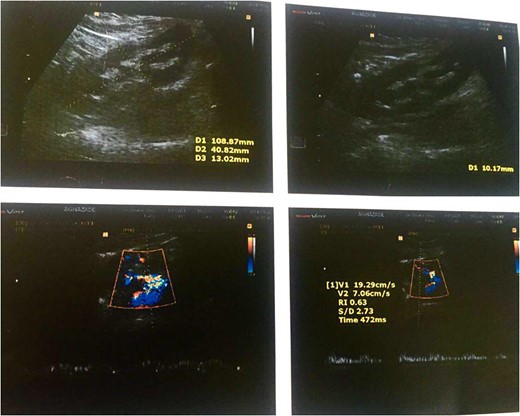

Color Doppler ultrasound of the transplanted kidney 2 months after surgery.

Color Doppler ultrasound of the transplanted kidney 2 months after surgery in the zoomed area of the image.